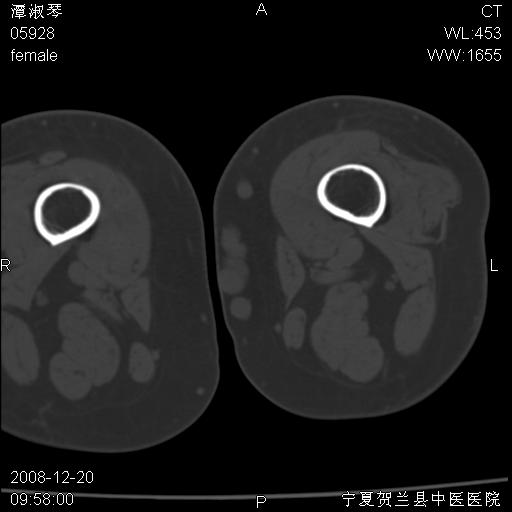

标题: CT17526:请各位看看是啥?

左胫骨下端松质骨及髓腔内可见点片状高密度灶,骨皮质无明显膨胀及变薄。病变范围较长。支持骨梗死,退行性骨关节病,膝关节积液

支持骨梗死,退行性骨关节病,膝关节积液.

左股骨下段骨梗死。双膝退变。